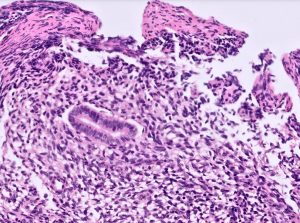

The biopsies showed small glands lined by simple columnar epithelium with cells showing basal elongated nuclei and scant apical eosinophilic cytoplasm. The surrounding stroma was cellular and composed of bland spindle cells with hyperchromatic nuclei with focal crush artefact. Keratin AE1/AE3 and PAX8 were expressed in the glandular cells only. The stromal cells were diffusely positive for CD10. ER was expressed in both glands and stroma. Neuroendocrine (NE) markers (synaptophysin, chromogranin A and INSM1), CD45, CD20, SS18-SSX and SSX-CT were negative. A diagnosis of ureteric endometriosis was rendered.

While the PAX8 positive bland glandular proliferation suggested nephrogenic metaplasia, the stromal proliferation suggested a biphasic lesion or dual pathology. The stromal cell cytomorphology was spindled rather than lymphoid; and while CD10 was diffusely positive, the CD45-/CD20-/ER+ immunoprofile excluded a B-cell lymphoproliferative disorder. Although the stromal cells showed focal crush artefact, they did not exhibit significant cytological atypia with high nuclear to cytoplasmic ratios, nuclear overlap and fine chromatin; and NE markers were negative, excluding small cell NE carcinoma. Co-expression of PAX8 and ER have been described in biphasic synovial sarcoma (BSS) and can be a diagnostic pitfall [5,6]. PAX8 was expressed in the glandular structures and ER was diffusely expressed in both glands and stroma in this case, however, the stromal cells did not exhibit fascicular architecture, there was no staghorn/hemangiopericytic branching vascular pattern, KRT AE1/AE3 was completely negative in the stromal cells, and SS18-SSX and SSX-CT were negative, excluding BSS.